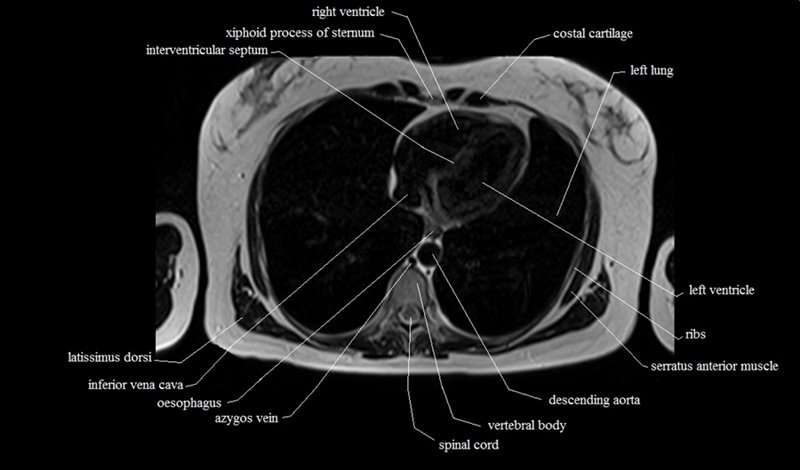

MRI Axial Cross Sectional Anatomy of Chest

This MRI chest (thorax) axial cross sectional anatomy tool is absolutely free to use. Use the mouse scroll wheel to move the images up and down, or alternatively, use the tiny arrows (→) on both sides of the image to navigate through the images. For a more detailed view, double-click the image to view it in full screen, and use the menu in the top right-hand corner to view individual slides or play them in a loop.